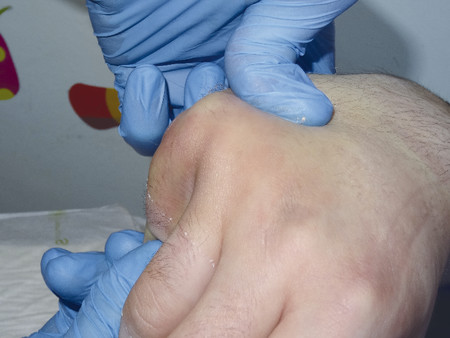

14.5 Fracture Dislocations of the Base of the Fourth and Fifth Metacarpals

These injuries can be easily missed and that is why it is essential to always examine three views (anteroposterior [AP], lateral, oblique) in the emergency department (Fig. 14‑10 a,b). They are inherently unstable and even after reduction under anesthesia the base of the fourth and fifth metacarpal will often re-dislocate even in a well-molded plaster cast.